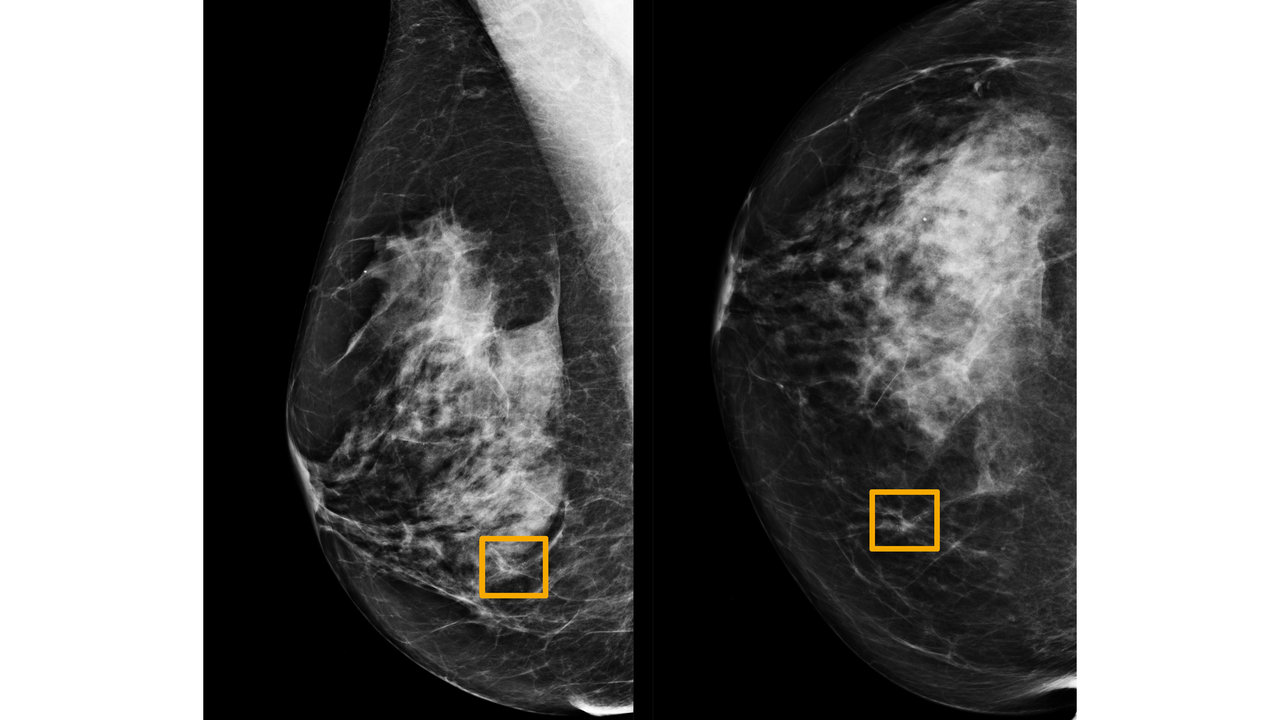

Artificial intelligence can help doctors do a better job of finding breast cancer on mammograms, researchers from Google and medical centres in the United States and Britain are reporting in the journal Nature. The new system for reading mammograms, which are X-rays of the breast, is still being studied and is not yet available for widespread use. It is just one of Google’s ventures into medicine. Computers can be trained to recognise patterns and interpret images, and the company has already created algorithms to help detect lung cancers on CT scans, diagnose eye disease in people with diabetes and find cancer on microscope slides. “This paper will help move things along quite a bit,” said Dr Constance Lehman, director of breast imaging at the Massachusetts General Hospital in Boston, who was not involved in the study. “There are challenges to their methods. But having Google at this level is a very good thing.” Tested on images where the diagnosis was already known, the new system performed better than radiologists. On scans from the United States, the system produced a 9.4 percent reduction in false negatives, in which a mammogram is mistakenly read as normal and a cancer is missed. It also provided a lowering of 5.7 percent in false positives, where the scan is incorrectly judged abnormal but there is no cancer. On mammograms performed in Britain, the system also beat the radiologists, reducing false negatives by 2.7 percent and false positives by 1.2 percent. Google paid for the study and worked with researchers from Northwestern University in Chicago and two British medical centres, Cancer Research Imperial Centre and Royal Surrey County Hospital. [caption id=“attachment_7849451” align=“alignnone” width=“1280”]

The yellow box indicates where cancer was spotted in the mammogram by AI, which radiologists failed to detect. Image: Northwestern University[/caption] Last year, 268,600 new cases of invasive breast cancer and 41,760 deaths were expected among women in the United States, according to the American Cancer Society. Globally, there are about 2 million new cases a year, and more than half a million deaths. About 33 million screening mammograms are performed each year in the United States. The test misses about 20 percent of breast cancers, according to the American Cancer Society, and false positives are common, resulting in women being called back for more tests, sometimes even biopsies. Doctors have long wanted to make mammography more accurate. “There are many radiologists who are reading mammograms who make mistakes, some well outside the acceptable margins of normal human error,” Lehman said. To apply artificial intelligence to the task, the authors of the Nature report used mammograms from about 76,000 women in Britain and 15,000 in the United States, whose diagnoses were already known, to train computers to recognise cancer. Then, they tested the computers on images from about 25,000 other women in Britain, and 3,000 in the United States, and compared the system’s performance with that of the radiologists who had originally read the X-rays. The mammograms had been taken in the past, so the women’s outcomes were known, and the researchers could tell whether the initial diagnoses were correct. “We took mammograms that already happened, showed them to radiologists and asked, ‘Cancer or no?’ and then showed them to AI, and asked, ‘Cancer, or no?’” said Dr Mozziyar Etemadi, an author of the study from Northwestern University. This was the test that found AI more accurate than the radiologists. Unlike humans, computers do not get tired, bored or distracted toward the end of a long day of reading mammograms, Etemadi said. In another test, the researchers pitted AI against six radiologists in the United States, presenting 500 mammograms to be interpreted. Overall, AI again outperformed humans. But in some instances, AI missed a cancer that all six radiologists found — and vice versa. “There’s no denying that in some cases our AI tool totally gets it wrong and they totally get it right,” Etemadi said. “Purely from that perspective, it opens up an entirely new area of inquiry and study. Why is it that they missed it? Why is it that we missed it?” Lehman, who is also developing AI for mammograms, said the Nature report was strong, but she had some concerns about the methods, noting that the patients studied might not be a true reflection of the general population. A higher proportion had cancer, and the racial makeup was not specified. She also said that “reader” analyses involving a small number of radiologists — this study used six — were not always reliable. The next step in the research is to have radiologists try using the tool as part of their routine practice in reading mammograms. New techniques that pass their initial tests with flying colours do not always perform as well out in the real world. “We have to see what happens when radiologists have it, see if they do better,” Etemadi said. Lehman said, “We have to be very careful. We want to make sure this is helping patients.” She said an earlier technology, computer-aided detection, or CAD, provided a cautionary tale. Approved in 1998 by the Food and Drug Administration to help radiologists read mammograms, it came into widespread use. Some hospital administrators pressured radiologists to use it whether they liked it or not because patients could be charged extra for it, increasing profits, Lehman said. Later, several studies, including one that Lehman was part of, found that CAD did not improve the doctors’ accuracy, and even made them worse. “We can learn from the mistakes with CAD and do it better,” Lehman said, adding that AI has become far more powerful, and keeps improving as more data is fed in. “Using computers to enhance human performance is long overdue.” She and Etemadi said that a potentially good use of AI would be to sort mammograms and flag those most in need of the radiologist’s attention. The system may also be able to identify those that are clearly negative, so they could be read quickly and patients could promptly be given a clean bill of health. Although developers of AI often say it is intended to help radiologists, not replace them, Lehman predicted that eventually, computers alone will read at least some mammograms, without help from humans. “We’re onto something,” she said. “These systems are picking up things a human might not see, and we’re right at the beginning of it.” Denise Grady c.2019 The New York Times Company